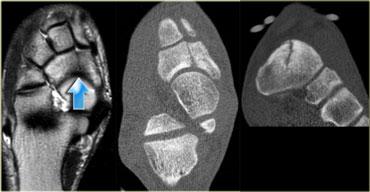

Bên trái là hình ảnh của bệnh nhân nữ 22 tuổi, vận động viên chuyên nghiệp với khởi phát đau vùng mu bàn chân gần đây, kéo dài sau khi tập luyện.

Tại thời điểm thăm khám, MRI cho thấy tăng tín hiệu trên chuỗi xung STIR và giảm tín hiệu trên chuỗi xung T1W (tức là gãy xương do stress độ 3).

Gãy xương do stress độ 4 tại xương thuyền. Chuỗi xung T1W và CT (ảnh cắt ngang và tái tạo mặt phẳng coronal)

Bên trái là hình ảnh của bệnh nhân nam 27 tuổi, cầu thủ bóng đá thi đấu ở giải nghiệp dư hạng cao nhất.

Bệnh nhân bị đau vùng giữa bàn chân với các triệu chứng gần đây có xu hướng tăng nặng.

Chuỗi xung T1W cho thấy đường gãy rõ ràng trong xương thuyền, gợi ý gãy xương do stress độ 4.

CT tương ứng cho thấy đường gãy và xơ cứng trên các ảnh cắt ngang và tái tạo mặt phẳng coronal.